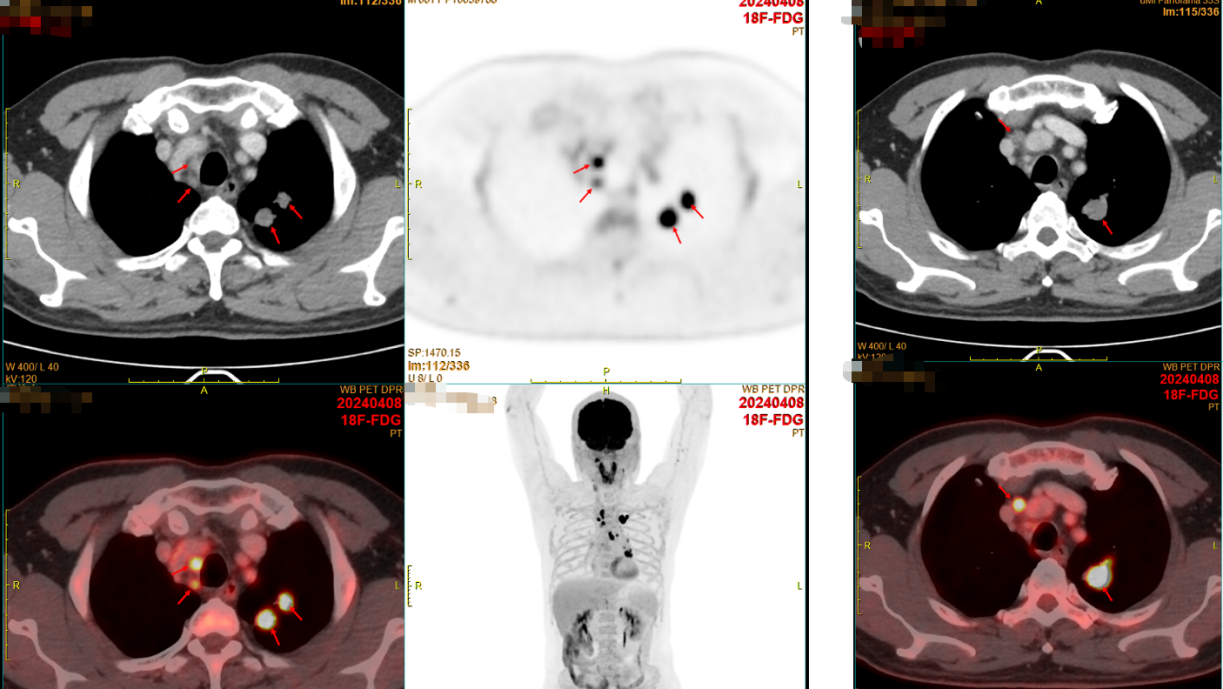

患者2024年2月感冒后出现咽痛、咳嗽、咳黄色粘痰,偶有痰中带血(7-8次/天,晨起明显),伴胸闷、活动后稍气促,偶有头晕、盗汗,未重视。2024年3月因咯血增多于当地医院就诊,胸CT提示肺占位。2024-04-08我院全身PET/CT示:

1.左肺上叶尖后段高代谢实性结节(2个结节融合),考虑周围型肺癌;

2.左侧肺门、纵隔(2R、3A、4L、6组)多发淋巴结转移;

3.左侧肾上腺结合部增粗,代谢增高,考虑转移瘤。

18F-FDG全身显像:左肺上叶尖后段高代谢实性结节(较大1.9×1.8×2.4cm),考虑周围型肺癌;左侧肺门、纵隔多发淋巴结转移;左侧肾上腺结合部稍粗,代谢增高,考虑转移瘤。

2024-04-08(初诊)vs 2025-03-07(复查)PET/CT:

左肺上叶尖后段实性结节体积缩小(较大约0.8×0.8×1.1cm vs 原1.9×1.8×2.4cm);

左肺门、纵隔多发淋巴结转移瘤体积缩小;

左侧肾上腺结合部增粗程度减轻。